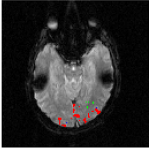

The Experience Based Cognition competition (EBC) (University of Pittsburgh, 2007) offers an opportunity to study complex responses to natural environments. The EBC datasets comprise three 20-minute runs (704 TRs in each run) of subjects interacting in an urban virtual reality environment. Subjects were audibly instructed to complete three search tasks in the environment: looking for weapons (but not tools) taking pictures of people with piercing (but not others), or picking up fruits (but not vegetables). The data was collected with a 3T EPI scanner (TR = s, xy dimension: , voxel size = mm, 34 slices with a thickness of mm). We analyze the second runs of subjects 14 and 13. For each subject, the matrix is composed of intra-cranial voxels at TRs. We first remove the non regionally specific variance captured by the first eigenmodes of a singular value decomposition of the dataset. We then compute using and . After embedding the dataset into four dimensions, we cluster the voxels. Figs. 18 and 20 display the datasets after embedding. Because we cannot display four dimensions, we show the projections of the dataset on three consecutive coordinates. All the coordinates contribute to the spread the dataset along elongated arms, which facilitates the clustering. Voxels that do not correspond to the background activity (the maroon cluster in Figs. 18 and 20) are superimposed on anatomically registered structural images and colored according to their cluster label (see Figs. 19 and 21). For both subjects, the clusters are connected regions (see Figs. 19 and 21), compactly organized around functional areas related to the processing of visual, and auditory stimuli (music, cellphone ringing, dog roaring) in the virtual environment. It is important to emphasize that our method never enforces any form of spatial proximity, and is purely based on functional connectivity.

For subject 14 (Fig. 19), the orange cluster corresponds to activation in the calcarine cortex associated with V1/V2 representations of the lower visual fields, while the light blue cluster corresponds to representations of the upper visual fields. Activation in lateral areas (visual motion areas, MT/V5) is also present, as well as activity in the posterior convexial cortex (area VP). The activation is predominantly in the right hemisphere. Interestingly, the two clusters located in the visual cortex (light blue and orange) have very similar and coordinates (see Fig. 18-left). The cyan cluster corresponds to activation in the right frontal gyrus (Broca area) associated with language comprehension. The yellow clusters are located in the right and left superior temporal gyri and medial temporal gyri (Wernicke area). These regions correlate with activation

in the auditory cortex and language areas. Finally, the dark blue cluster corresponds to activation in the prefrontal cortex. A very similar pattern of activity (Fig. 21) was obtained for subject 13. The blue and orange clusters, located in the calcarine cortex, correspond to V1 and V2 areas. Again, these two clusters, both located in the visual cortex, have similar and coordinates. The green cluster is located in the medial temporal gyrus (Wernicke area) and is associated with language processing.